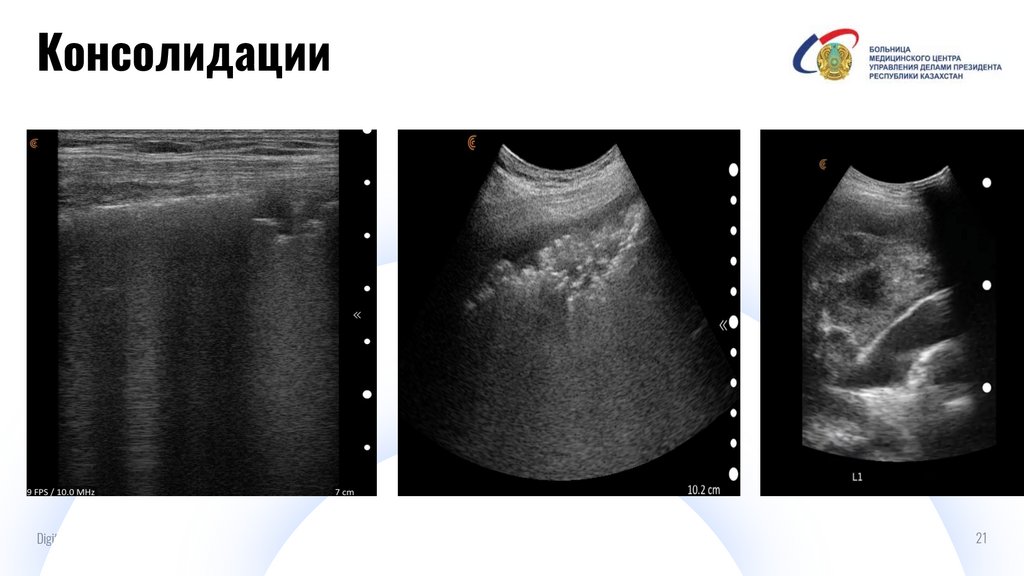

Консолидации

И

Digital IT pitch-deck PowerPoint bundle

21